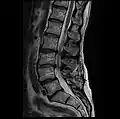

MRI lumbar spine pre-hemilaminectomy (sagittal T2 FRFSE)

-

MRI lumbar spine pre-hemilaminectomy (sagittal T1 FSE)